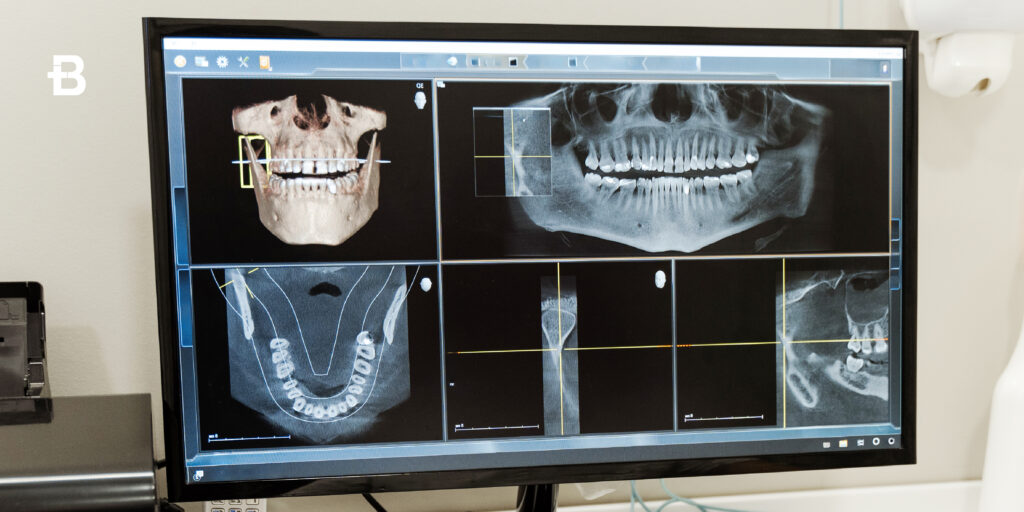

La TAC Cone Beam dentale è una tecnologia di imaging avanzata che sta rivoluzionando il campo dell’odontoiatria. Grazie alla sua capacità di ottenere immagini tridimensionali ad alta risoluzione, la TAC Cone Beam consente ai dentisti di visualizzare in modo dettagliato la struttura dentale e ossea del paziente, migliorando la precisione diagnostica e il trattamento. Ma cos’è esattamente questa tecnologia? In che modo si differenzia dalle radiografie tradizionali? E quando viene prescritta dal dentista? In questo articolo esploreremo a fondo la diagnostica 3D odontoiatrica, analizzando il funzionamento della TAC Cone Beam, le sue applicazioni e i vantaggi che offre ai pazienti. Cos’è la TAC Cone Beam La TAC Cone Beam dentale, conosciuta anche come Tomografia a Fascio Conico, è una tecnica di imaging avanzata che utilizza raggi X per produrre immagini 3D della bocca, dei denti e delle strutture circostanti, come ossa, nervi e tessuti molli. A differenza delle tradizionali radiografie, che offrono immagini bidimensionali, la TAC Cone Beam fornisce immagini tridimensionali che permettono ai dentisti di analizzare in dettaglio la struttura anatomica del paziente. Il dispositivo per la TAC Cone Beam dentale è costituito da un macchinario che emette raggi X in forma di cono, da cui il nome “Cone Beam”. Il paziente viene posizionato al centro del dispositivo, e durante la scansione il fascio di raggi X ruota attorno alla testa del paziente, acquisendo diverse immagini da diverse angolazioni. Successivamente, un software specializzato elabora questi dati per creare immagini 3D ad alta risoluzione. Queste immagini permettono di ottenere informazioni molto più precise rispetto alle tradizionali radiografie bidimensionali, facilitando diagnosi accurate e trattamenti mirati. Differenze rispetto alla radiografia Le principali differenze rispetto alla radiografia tradizionale risiedono nella qualità e nel tipo di immagine che viene acquisita. Mentre una radiografia convenzionale fornisce una visione bidimensionale delle strutture dentali e ossee, la TAC Cone Beam dentale offre un’immagine tridimensionale che permette una valutazione molto più completa e dettagliata. Immagini 3D vs 2D: La radiografia tradizionale fornisce solo una rappresentazione in due dimensioni delle strutture interne della bocca. Al contrario, la TAC Cone Beam crea una mappa tridimensionale, che consente ai dentisti di vedere le strutture da diverse angolazioni e di esaminare la posizione e la condizione di denti, ossa e nervi con maggiore precisione. Maggiore risoluzione e dettagli: La TAC Cone Beam è in grado di acquisire immagini con una risoluzione molto più alta rispetto alle radiografie tradizionali. Ciò consente ai professionisti di osservare dettagli fini, come la densità ossea, la forma delle radici dentali e la posizione dei nervi, che potrebbero non essere visibili con le radiografie convenzionali. Riduzione della distorsione: Le radiografie tradizionali possono presentare distorsioni, in particolare nelle immagini 2D delle strutture più complesse, come le radici dei denti. Con la TAC Cone Beam, questa distorsione è notevolmente ridotta grazie alla visualizzazione in 3D, che rende le immagini più accurate e affidabili. Esposizione ridotta a radiazioni: Un altro vantaggio significativo della TAC Cone Beam rispetto alle tradizionali TAC a spirale è che la quantità di radiazioni emesse è significativamente inferiore, rendendo la procedura più sicura per il paziente, pur mantenendo una qualità dell’immagine elevata. Quando viene prescritta La TAC Cone Beam dentale viene prescritta in specifiche situazioni cliniche, quando il dentista ha bisogno di informazioni più dettagliate e precise rispetto a quelle che possono essere ottenute con le radiografie tradizionali. Alcuni dei principali casi in cui viene prescritta includono: Implantologia dentale: La TAC Cone Beam è uno degli strumenti più utili nella pianificazione di impianti dentali. Fornisce una visione completa della struttura ossea e aiuta a determinare la posizione migliore per l’impianto, evitando danni ai nervi o ad altri elementi sensibili. Diagnosi di infezioni o malformazioni: Se un paziente presenta sintomi di infezioni ossee, cisti o altre anomalie strutturali, la TAC Cone Beam può aiutare a identificare la causa e a pianificare il trattamento. La visualizzazione 3D permette di vedere la dimensione e la posizione delle infezioni, facilitando la diagnosi. Patologie parodontali: Per valutare la gravità delle malattie parodontali e la perdita ossea associata, la TAC Cone Beam consente una visione precisa della struttura ossea del paziente, determinando l’estensione della malattia e aiutando a decidere il trattamento più adatto. Chirurgia orale e maxillo-facciale: In chirurgia orale, la TAC Cone Beam è fondamentale per la pianificazione pre-operatoria di interventi chirurgici complessi, come la rimozione di tumori o la correzione di anomalie strutturali della mascella e del viso. Valutazione dei denti del giudizio: La TAC Cone Beam è particolarmente utile per studiare la posizione dei denti del giudizio, specialmente quando sono inclusi o posizionati in modo anomalo, per evitare complicazioni durante l’estrazione. Trattamenti ortodontici: La diagnostica 3D odontoiatrica è anche importante per la pianificazione di trattamenti ortodontici complessi, poiché fornisce una visione dettagliata dell’allineamento dei denti e della struttura ossea, migliorando l’efficacia del trattamento. Vantaggi per il paziente La TAC Cone Beam dentale offre numerosi vantaggi sia per il dentista che per il paziente. Alcuni dei principali benefici includono: Maggiore precisione diagnostica: Le immagini 3D ad alta risoluzione permettono al dentista di esaminare dettagli che non sarebbero visibili con le radiografie tradizionali. Questo consente diagnosi più accurate e trattamenti più mirati. Riduzione dei tempi di trattamento: Poiché la TAC Cone Beam fornisce immagini rapide e dettagliate, il trattamento può essere pianificato in modo più efficiente, riducendo il numero di visite e i tempi complessivi di trattamento. Minore esposizione alle radiazioni: Rispetto ad altri tipi di TAC, la TAC Cone Beam emette una dose di radiazioni significativamente inferiore, riducendo i rischi per la salute del paziente. Miglioramento dell’estetica e della funzionalità: Grazie alla precisione delle immagini ottenute, la TAC Cone Beam consente di ottimizzare i trattamenti, come l’implantologia o la chirurgia maxillo-facciale, migliorando sia il risultato estetico che la funzionalità del sorriso. Maggiore comfort e velocità: La scansione con la TAC Cone Beam è rapida e meno invasiva rispetto ad altre tecniche di imaging, riducendo il disagio per il paziente. Prenota un consulto Prenota un consulto gratuito presso uno dei nostri centri Bludental per ricevere assistenza personalizzata dai nostri medici odontoiatri.